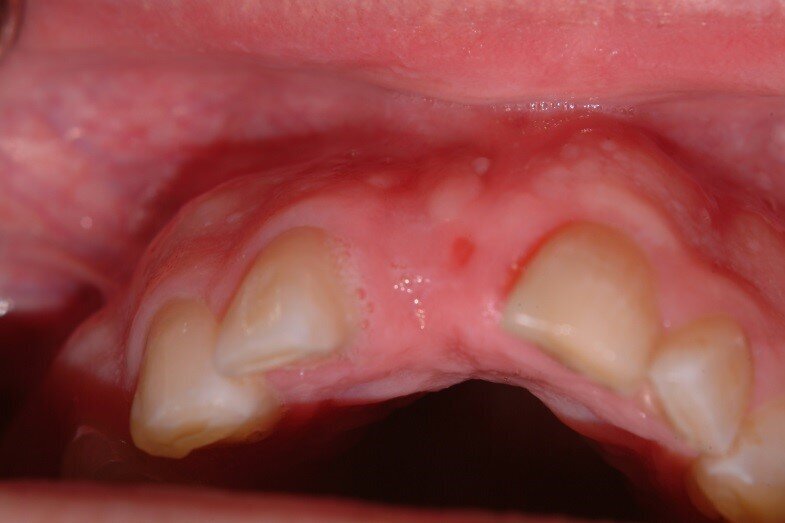

5. Bilateral pedicles using adjacent papilla to cover the connective tissue surfaces of the tuberosity graft (Fig. 5)

7. Monitoring of soft tissue healing. Tissue from the tuberosity and adjacent papillae gives a better match than palatal tissue. We are ready to re-enter when incision lines fully closed. (Fig. 6, 7)